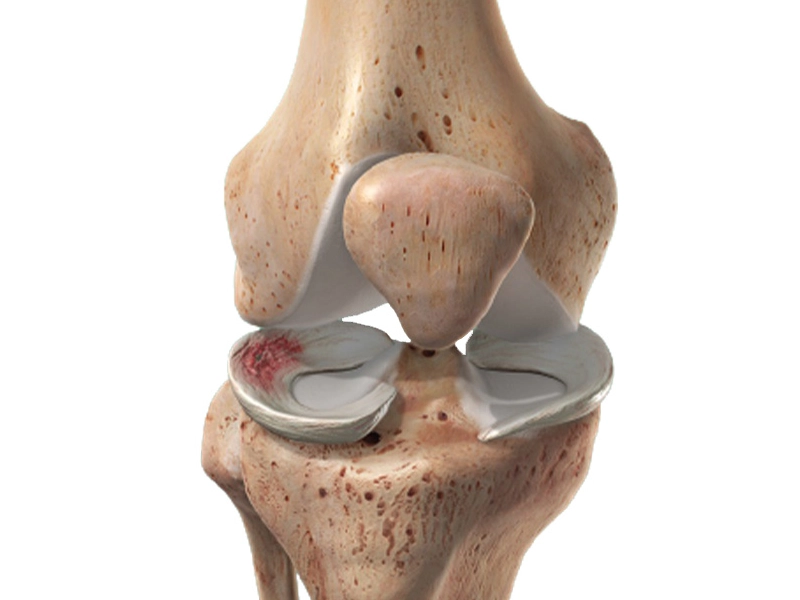

آرتروز زانو یا ساییدگی زانو چیست؟ (درک دقیق بیماری)

آرتروز زانو، که به عنوان استئوآرتریت (Osteoarthritis – OA) نیز شناخته میشود، شایعترین نوع آرتریت است و اساساً یک بیماری تخریبی است که غضروف مفصل زانو را تحت تأثیر قرار میدهد.

۱. نقش حیاتی غضروف در مفصل زانو

- غضروف مفصلی: یک بافت صاف، لغزنده و ارتجاعی است که انتهای استخوانها (ران و ساق) را در مفصل زانو میپوشاند.

- وظیفه غضروف: عملکرد اصلی غضروف، جذب ضربه و کاهش اصطکاک است؛ به طوری که حرکت زانو به نرمی و بدون درد انجام شود.

۲. فرایند تخریب در آرتروز زانو

در بیماری ساییدگی زانو، این غضروف حیاتی شروع به نرم شدن، نازک شدن و در نهایت از بین رفتن میکند.

- اصطکاک استخوان به استخوان: با از بین رفتن غضروف، استخوانهای مفصل زانو دیگر توسط یک لایه نرم محافظت نمیشوند. این امر باعث میشود استخوانها مستقیماً روی هم ساییده شوند (همان ساییدگی زانو) و این سایش، منبع اصلی درد، التهاب و سفتی است.

- تشکیل خارهای استخوانی (Osteophytes): در واکنش به آسیب غضروف، استخوان تلاش میکند خود را ترمیم کند و این اغلب منجر به رشد استخوانهای اضافی در لبههای مفصل میشود که به آنها خار استخوانی میگویند.